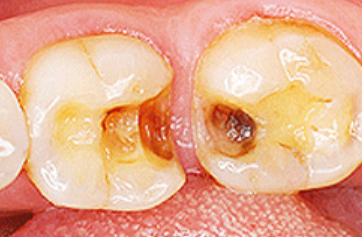

교합하는 치아 중

하중을 많이 받는

부위가

손상된

경우